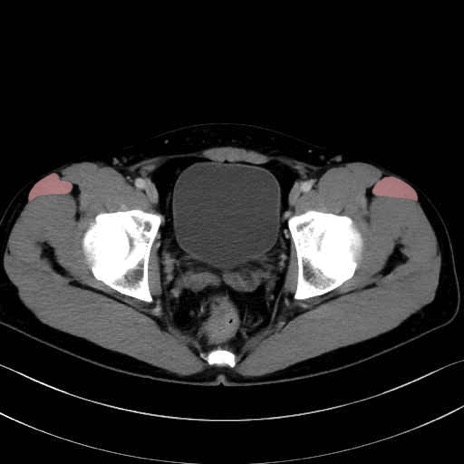

大腿筋膜張筋 (Tensor fasciae latae)